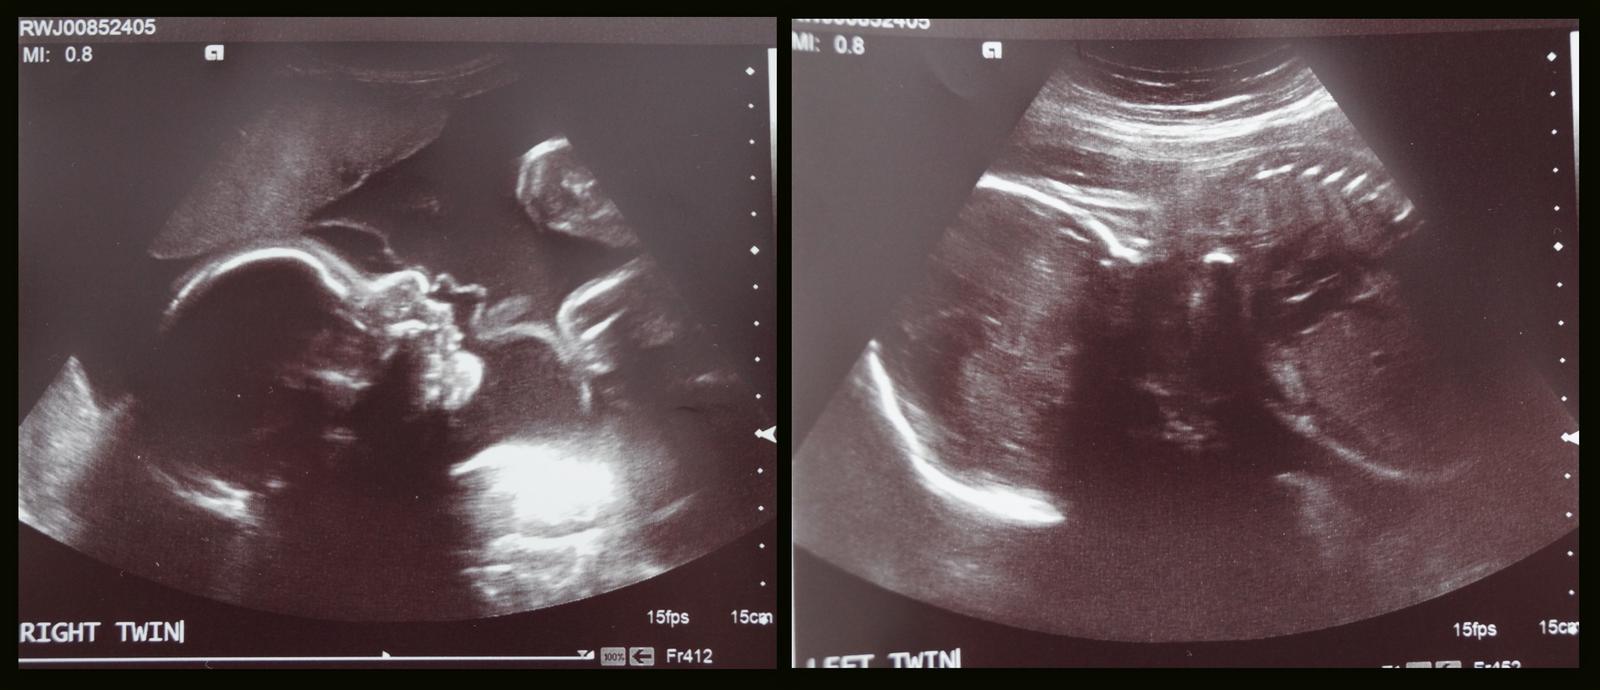

Ahoj holky 🙂 Co u vas noveho? My jsme byli vcera na UTZ ve 28tt, kluci krasne rostou a odpovidaji tydnum, tak jsem stastna, ze se jim dari. Doufam, ze spolu vydrzime jeste tech dalsich 10 tydnu 😝 Tajne prani, snad i splnitelne. Mame jen dve fotky, to ta minula dr nam jich nacvakala mnohem vice. Jeden chlapecek se ukazal krasne, druhy byl otoceny a lepe se ukazat proste nechtel...no co uz, tak snad na dalsim UTZ ve 32tt se ukaze lepe 🙂